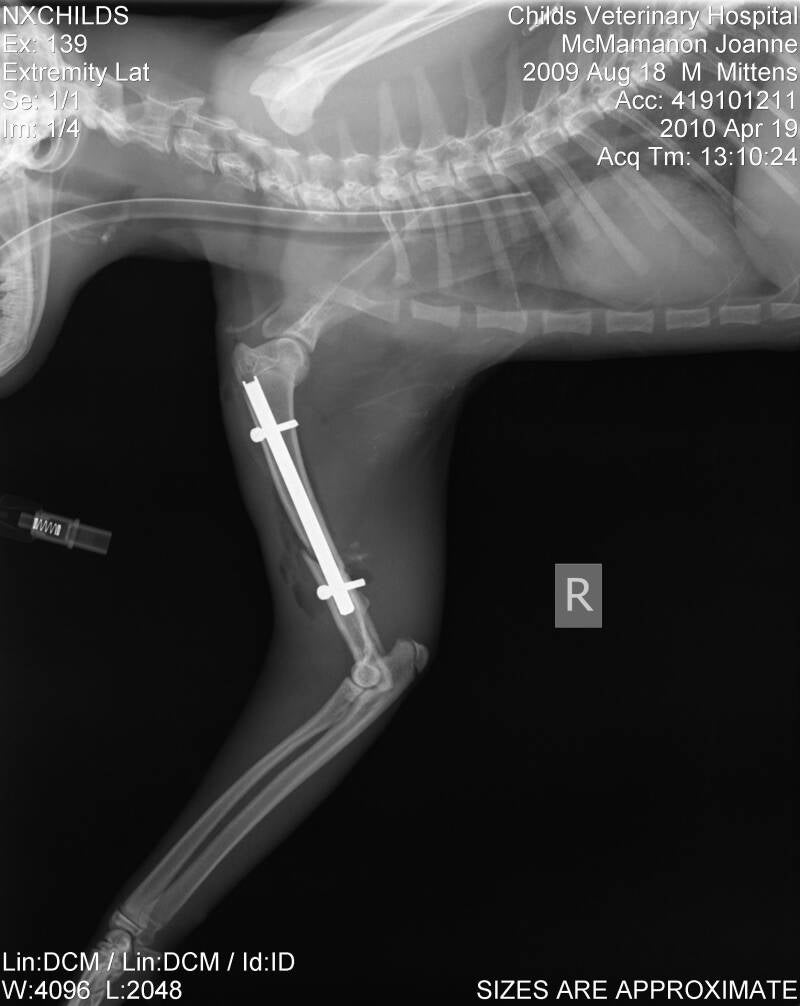

Interlocking Nail

The interlocking nail technique can be used when there is a long bone fracture in a bone such as the humerus.

The interlocking nail is a specialized pin that is placed inside the bone and locked into place with bone screws.  The screws go through the bone and the nail so that the nail is unable to slide out and the bone fragments cannot rotate around the nail.  The nail is left in place for the life of the animal.

Fracture healing generally requires 8-12 weeks.  During this time, activity should be limited so that the repair does not break down.  X-rays are taken to assess how the bone is healing.  When there is adequate callus formation on the bone, activity is usually allowed unrestricted afterward.